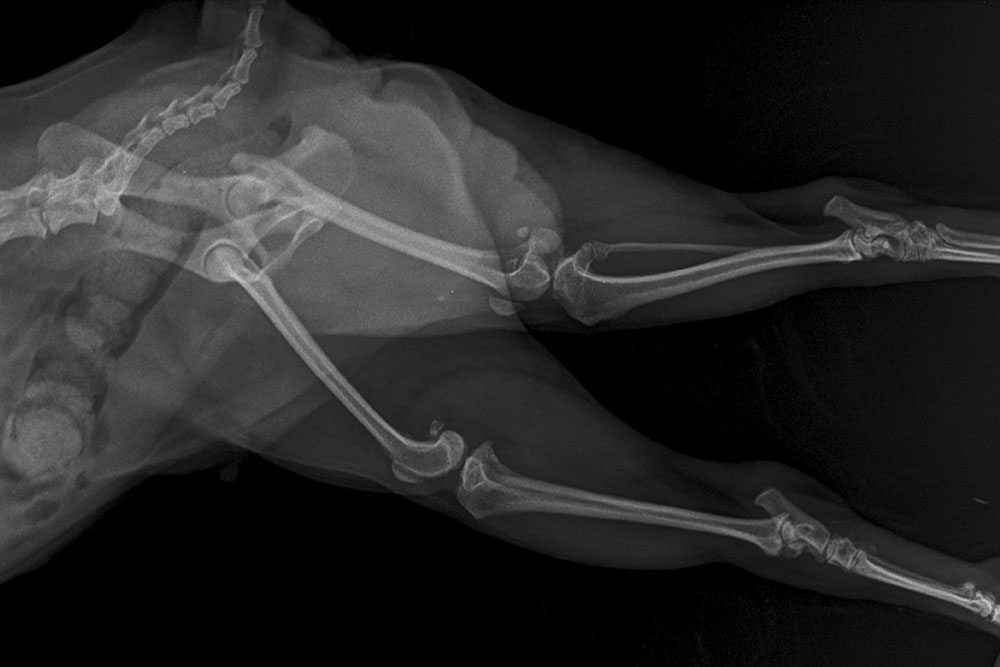

X-ray imaging helps evaluate the chest, abdomen, and skeleton. It can show heart enlargement, lung changes, organ size differences, masses, bladder stones, and arthritis. Radiographs confirm what we suspect on exam and help explain symptoms like weight loss or mobility changes.

Ultrasound imaging looks inside organs in real time and can find masses, cysts, stones, and inflammation that X-rays may not show. It’s also useful to guide needle sampling when needed. Imaging pairs with blood work to give both function and structure, creating a complete picture for planning care.

How do we assess arthritis and mobility issues?

We combine your observations with a gait exam and radiographs to judge arthritis severity. Multimodal pain management works best: medications for inflammation and pain, joint supplements, weight control, and targeted rehab exercises for osteoarthritis. Our rehabilitation and Eastern Medicine options include acupuncture, cold laser, and therapeutic exercises tailored to your pet.